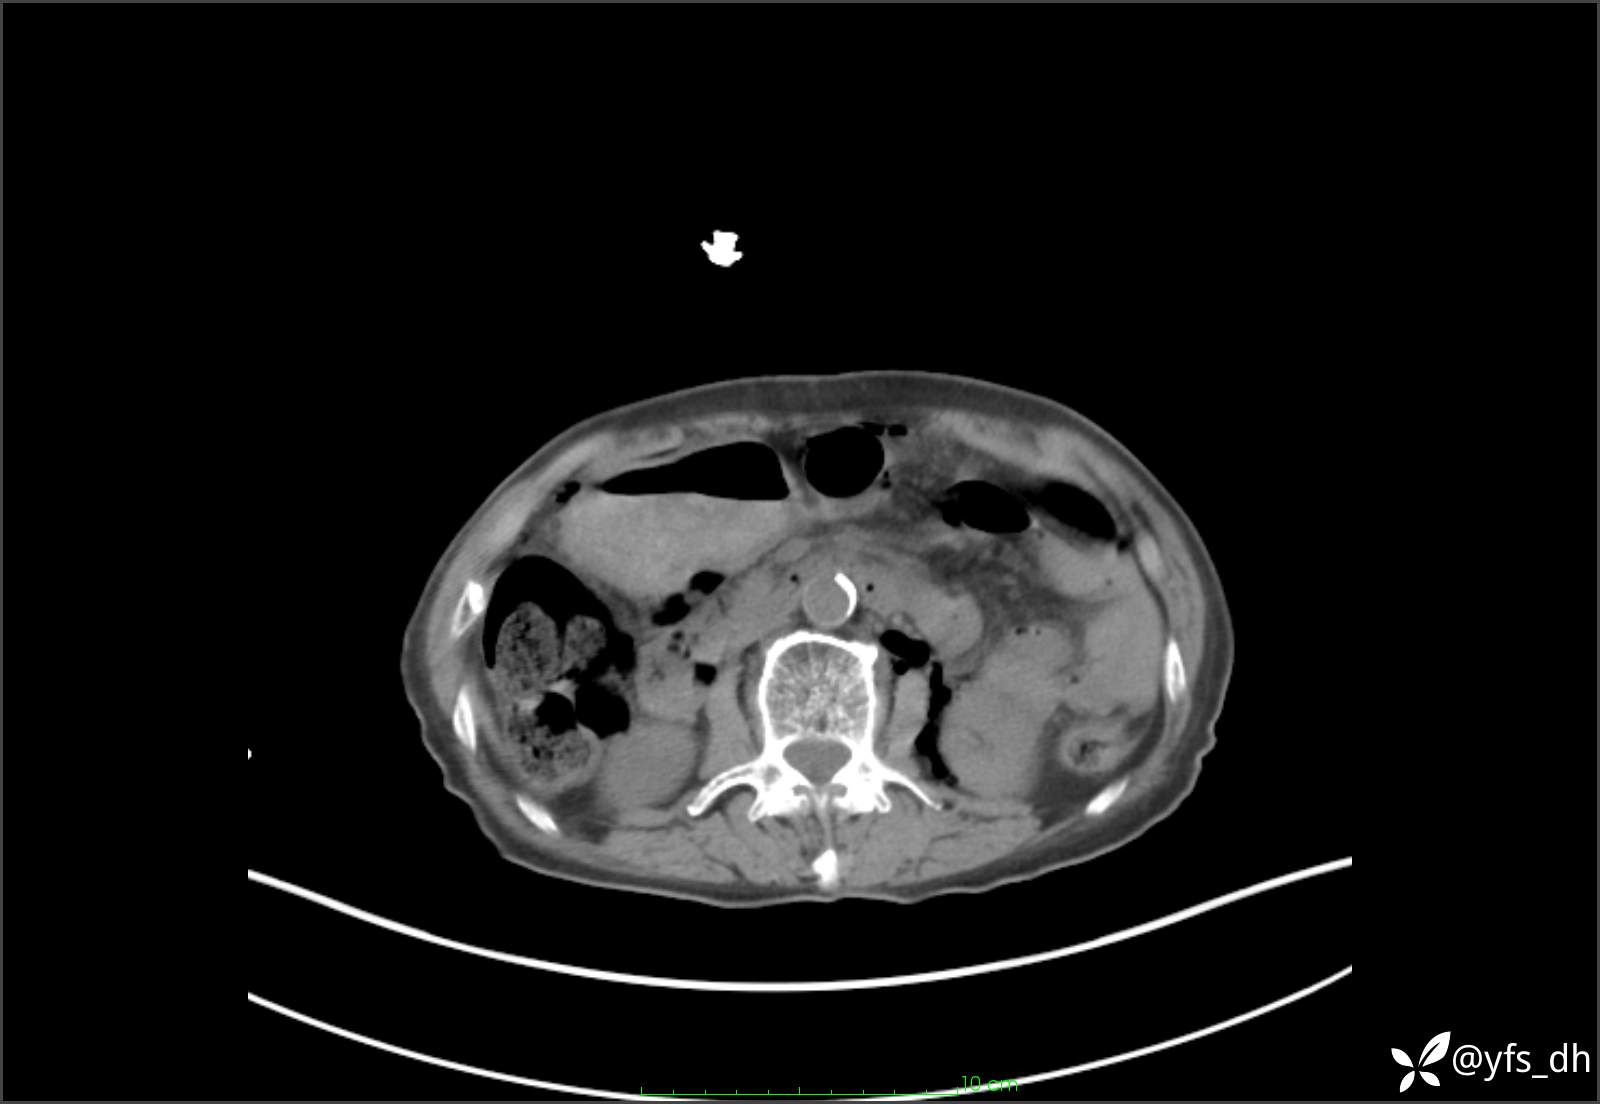

1.简要病史:患者4天前突发上腹部疼痛不适,但可以忍受。3小时前饭后突然加重,不能忍受后就诊。

2.简要手术记录:术中见腹盆腔大量肠液及粪便,乙状结肠中下段见一约3cm的破口。